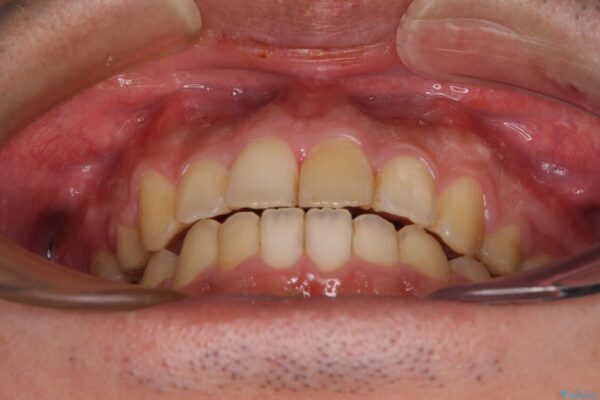

高校時代に行った抜歯矯正が後戻りをしたとのことで来院された患者様です。

下顎骨が左側に変位しているため、正中が合わないことは予想できましたが、歯列が整った後も咬み合わせが安定せず、咬み合わせを落ち着かせるために1年以上の期間を要しました。

治療前

• 後戻りでデコボコの前歯 インビザライン矯正治療 治療前画像